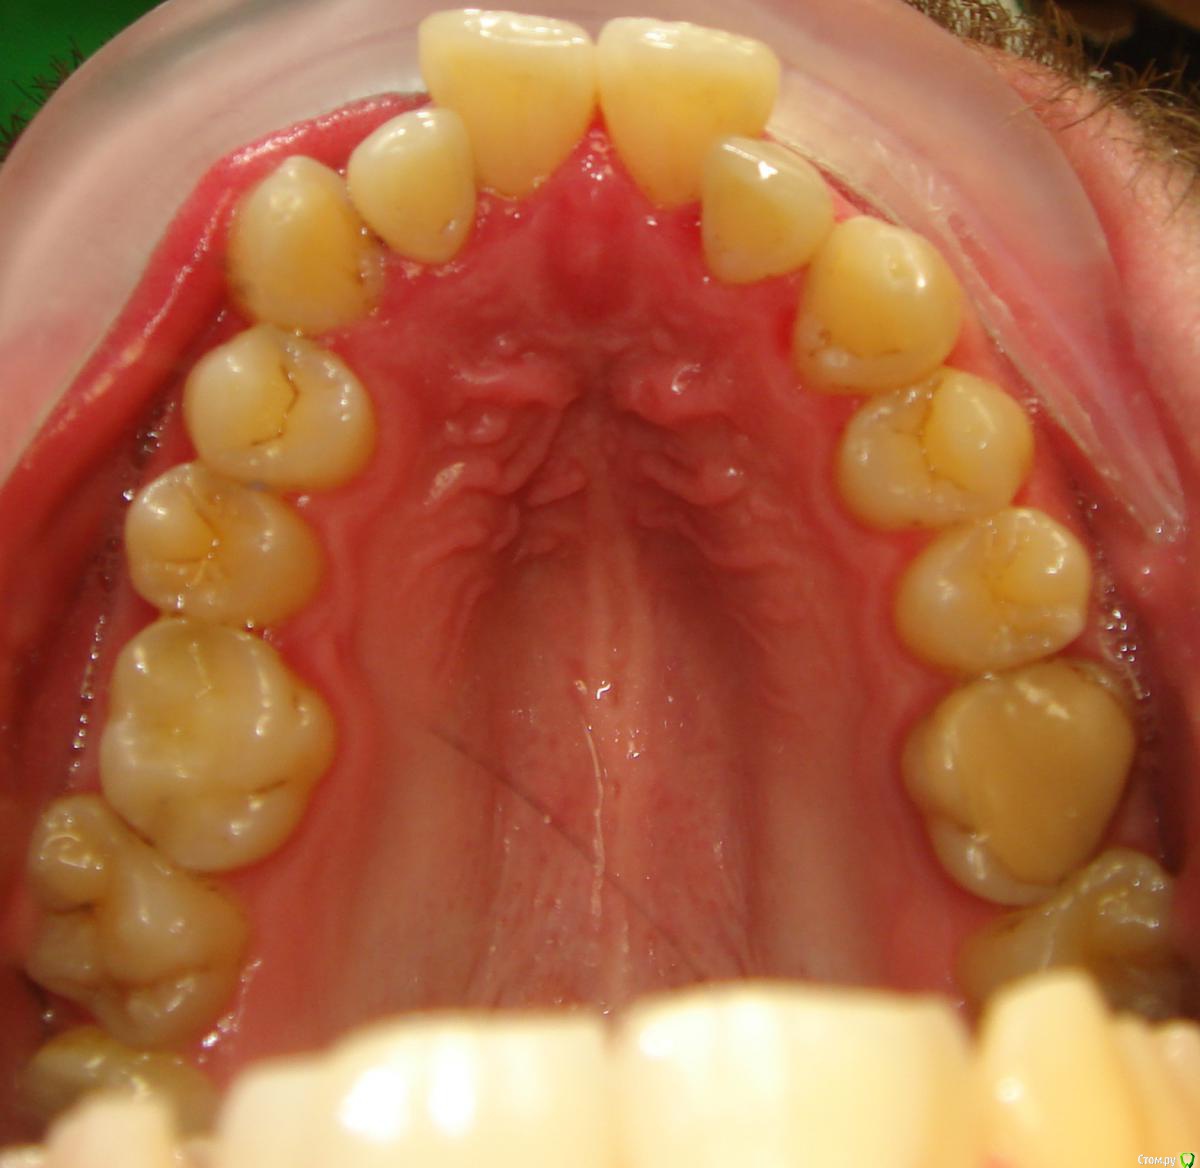

Здравствуйте, Коллеги. Вот такой вот случай, пациент 32 года. Изначально, хотел дистализировать в первом сегменте с целью апрайтинга 13 - 16, провести апрайтинг боковых зубов н/ч, затем САРПЕ и MEAW, понятно, что восьмерки долой еще до лечения. Но потом увидел форму корней 37, 47 (это не искажение, по КТ они и правда такие) и кисты прорезывания за ними. В связи с этим мне кажется, что апрайтинг снизу невозможен, так как эти верхушки никуда меня не пустят, разве что ввиду проблем с пародонтом семерки тоже уйдут. Вопрос: что делать??? Даже если отбросить мультилуп и готовить его на ортогнатию, то апрайт все-равно нужен, как поступить? Заранее спасибо!

P.S.: Забыл... сверху семерки такие же.